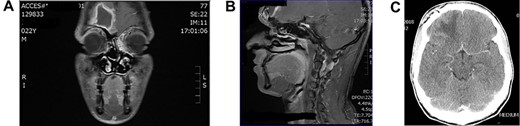

Young girl presented with unresolving sinusitis associated with fever, headache, vomiting and drowsiness. Diagnosed on CT brain as a case of SDE (Fig. 3A and B) as a complication of frontal sinusitis. The patient was managed by systemic intravenous antibiotic. Endoscopic frontal sinusotomy and frontal mini craniotomy to drain the empyema by the neurosurgery team. The patient recovered well with no complications as shown in follow-up CT scan (Figure 3C).

(A) axial CT brain with subdural empyema, (B) sagittal CT scan with subdural empyema and (C) post drainage CT brain with complete resolution of subdural empyema.